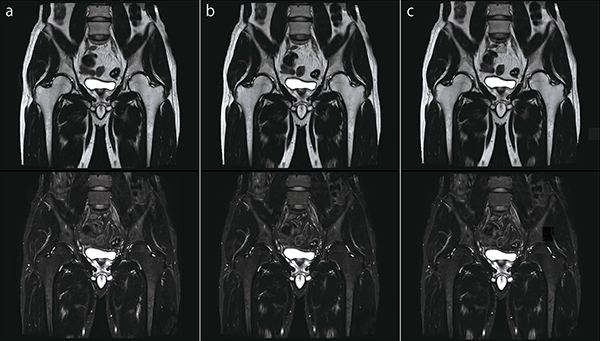

●股関節FatSep T2WI

図6 aは,IP-RAPIDを使用していない画像です。それに対して図6 bは,IP-RAPIDを使用している画像です。RAPID(Phase)の倍速数によって撮像時間短縮の調整を行い,RAPID(IP-Recon)強度の選択によって画像のSNRと空間分解能の調整を行います。また,図6 cもIP-RAPIDを使用している画像で,bよりもRAPID(Phase)の倍速数を上げて撮像時間を短縮しています。RAPID(Phase)の倍速数を大きく上げる場合には,SNRと空間分解能のバランスを考慮しながら,適切なRAPID(IP-Recon)強度を選択してください。

図6 股関節FatSep T2WI(上段:in Phase画像,下段:脂肪抑制画像)

a:IP-RAPID off, Phase=1.1, Freq/Phase=256×256, scan time=2:49

b:IP-RAPID on, Phase=1.6, IP-Recon=Light, Freq/Phase=256×256, scan time=1:58

c:IP-RAPID on, Phase=2.5, IP-Recon=Medium, Freq/Phase=256×256, scan time=1:18